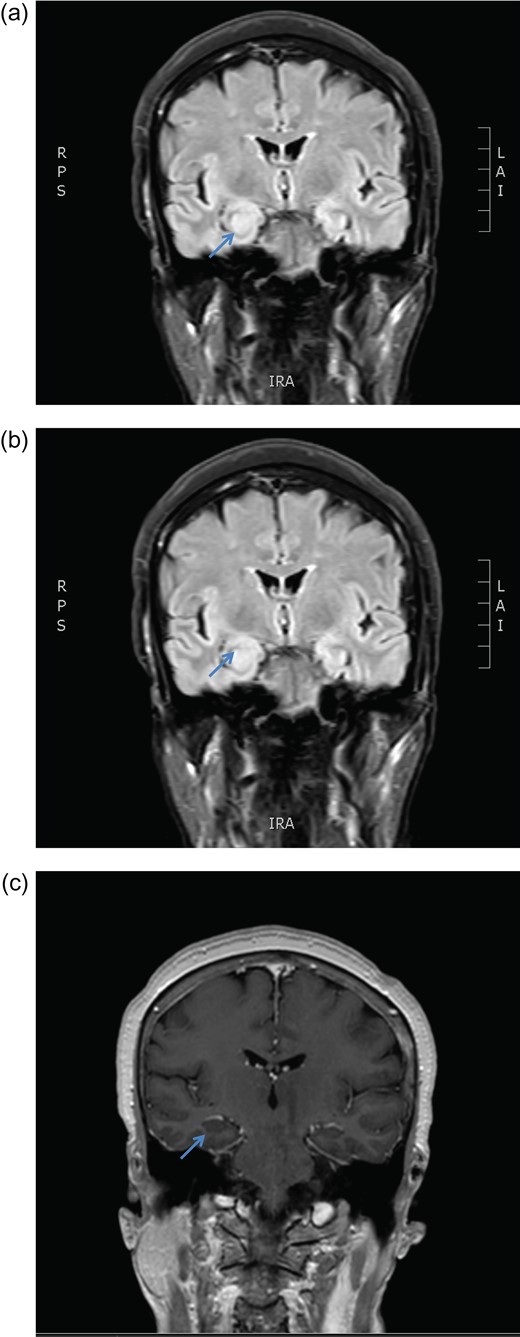

MRI brain coronal T2 FLAIR sequence depicting persistent right hippocampal high signal change in January (a) and March (b) 2016. There is no enhancement post gadolinium injection (c).

December 2015, she had a normal electroencephalogram (EEG). Subsequent MRI done January and March 2016 showed T2 Weighted Imaging Fluid Attenuated Inversion Recovery (T2WI/FLAIR) changes in the right medial temporal lobe (Fig. 2). Right hippocampal signal change was suspicious of low-grade glioma with a differential diagnosis of post viral limbic encephalitis. There was no enhancement with intravenous gadolinium administration and no other suggestion of a focal malignant disease. She remained clinically well and repeat MRI done October 2016 showed areas of signal abnormalities focused around the posterior horns of the lateral ventricles and but no sign of right temporal lobe low-grade glioma or encephalitis (Fig. 3). All of these signal changes resolved completely with repeated MRI and she had no further seizures.